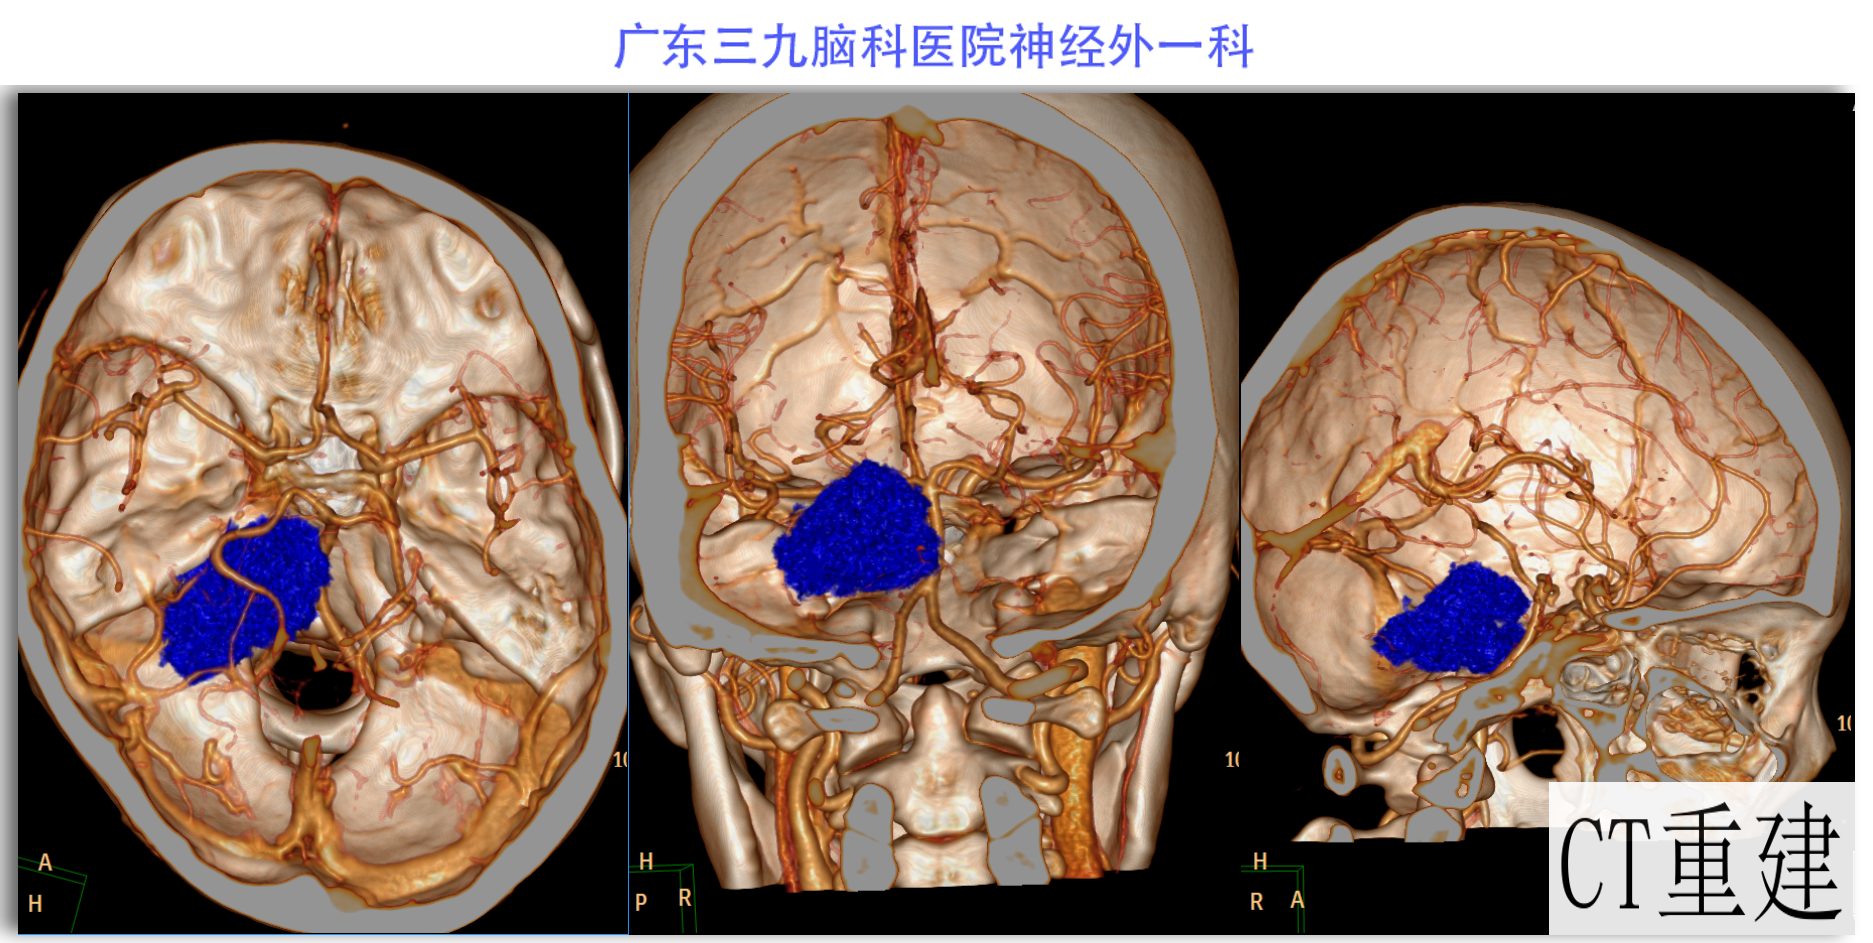

陈某某,女,41岁,因“左侧面部麻木3月余,吞咽困难半月余”于2024-02-17入院。患者3个月前出现左侧面部麻木,偶尔伴有头晕和左侧流泪,但没有听力下降或耳鸣。同时,患者也出现肢体乏力和行走不稳,但未接受任何治疗。半个月前,患者发现吞咽硬质食物稍有困难,同时左侧面部麻木加重。因此,前往当地医院就诊,并进行头颅MR检查,结果显示左侧CPA区存在占位性病变。为了进一步治疗,患者转诊至我院就医。术前检查显示:左侧角膜反射减弱,左侧鼻唇沟略微变浅,伸舌稍微右偏,咽反射迟钝。门诊诊断为“左侧巨大听神经瘤”,收治至我科进行住院治疗。手术过程顺利,术后患者恢复良好,面部轻度瘫痪与术前相同。术后病理检查结果确认为听神经瘤。